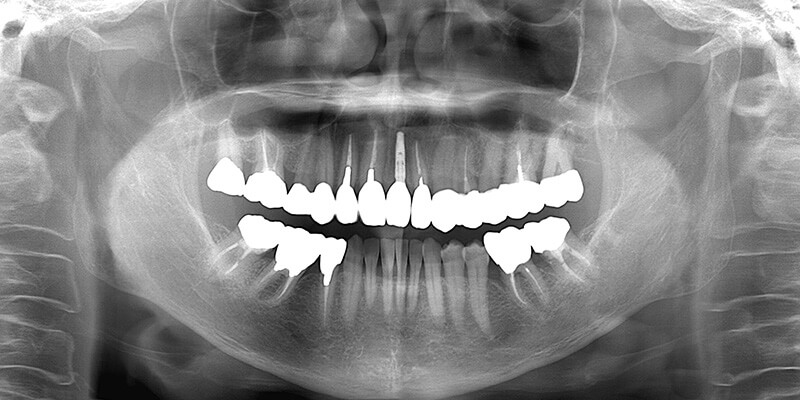

| 診査診断 | 上顎歯牙欠損、歯周病、不良補綴、根尖性周囲炎。 不正咬合により噛み合わせのバランスが悪い事が原因により咬合治療が必要。 |

| 治療内容 | 欠損部インプラント 不正咬合に対し不良補綴のやり直しと合わせて咬合再構築 |

| 治療期間 | 4ヶ月 |

| 費用 | 200万円 |

| 診査診断 | 歯周病、歯の崩壊、不良補綴。 全顎的咬合異常、前歯の噛み合わせ、奥歯の噛み合わせに問題あり。 |

| 治療計画 | 欠損部インプラント 不良補綴のやり直しと欠損部インプラント。 咬合の再構築、なるべく歯を残せる様に治療計画を立案。 |

| 治療期間 | 6ヶ月 |

| 費用 | 290万円 |